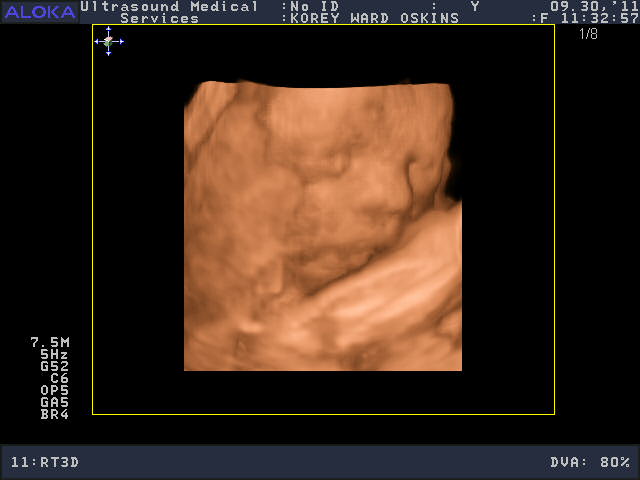

He was a very stubborn baby, so it was really kind of nerve-wracking at first thinking we might not get a single good picture. His face was squished up against the placenta and he wouldn’t budge. You’ll see that in the pictures below; it looks like an enveloping cloud or a scallop shell. Finally he moved a bit and we got some glimpses of his face. We saw him make some facial expressions, wiggle his fingers, and move his mouth around. We were curious to see whose nose he would have, and in some pictures, it looks like he has Josh’s, in others, mine.

So who do you think he looks like?

He is sooooo cute! Personally, I think he looks like ME.